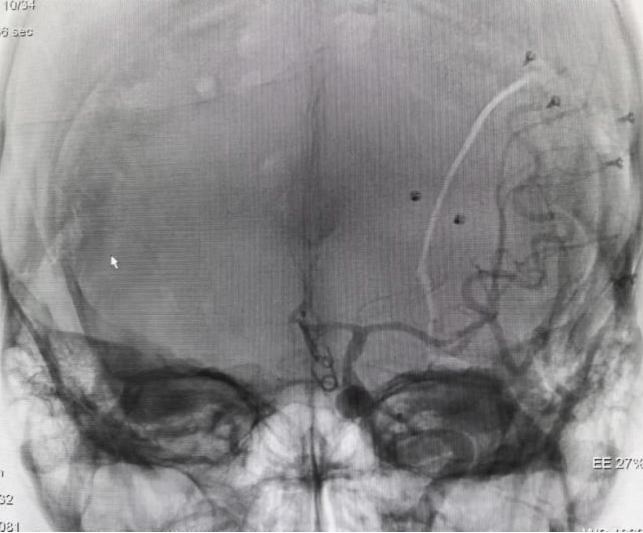

术前DSA提示前交通动脉瘤

迅速完善术前检查后,急诊行全脑血管造影检查提示前交通动脉瘤。虽然大多数前交通动脉瘤可通过神经介入栓塞微创处理,但此患者动脉瘤微小,且有子瘤,累及三支分支血管,栓塞术中动脉瘤破裂和缺血的风险极大,开颅显微镜下夹闭颅内动脉瘤是优选择。